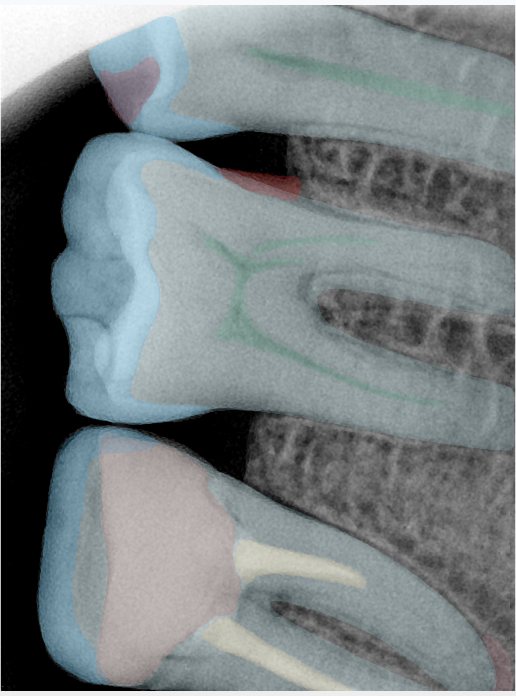

CR/DR 牙齿分割阶段记录

当前进展

- 完成了 CR/DR 牙齿相关分割训练

- 当前结果已经达到阶段预期,但仍有细节问题需要继续处理

相关测试

遇到的问题

- 训练过程中出现过 mask 下移问题

- 部分结果会出现 box 填充异常

- mask 边缘仍然有比较明显的锯齿感

参考

第二版算法问题测试